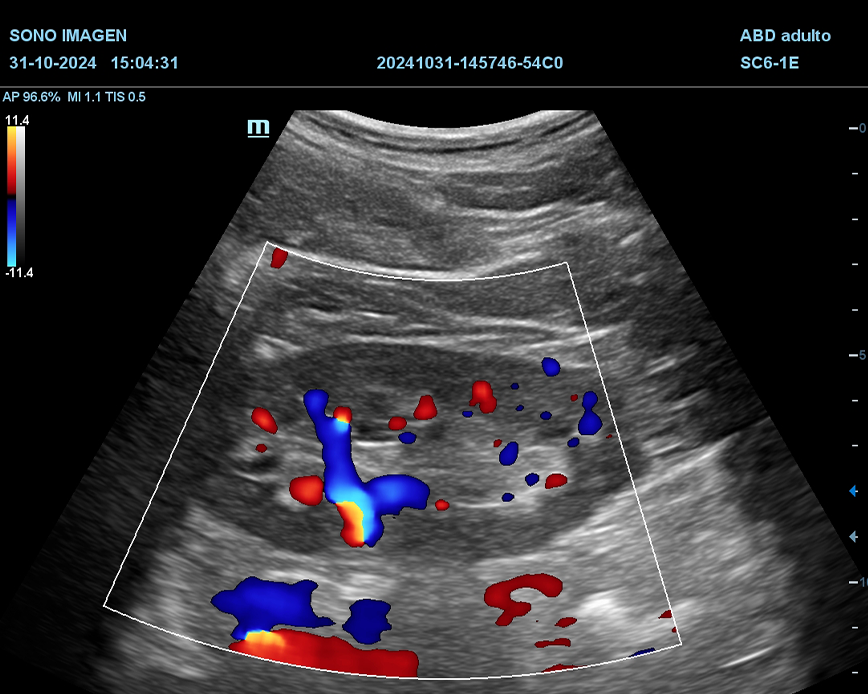

Ecografía Prostática

- hiperplasia prostática benigna(HPB)

- cáncer de próstata

- prostatitis

- dificultad para orinar o retención urinaria

- hematuria

- alteraciones en la fertilidad masculina

- control postquirúrgico o postratamiento

- anomalías detectadas en estudios previos

- quistes prostáticos